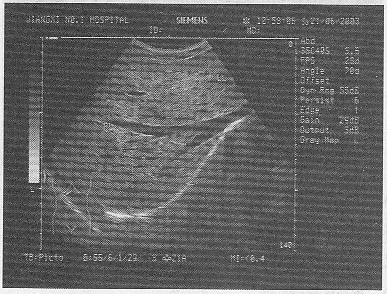

2.某患者25岁,高热,肝区疼痛。肝脏声像图表现如图,结合病史,最可能的诊断是![]() |

| 正确答案:B 解题思路:高热,肝区疼痛,声像图显示肝内可见一无回声暗区,壁厚,内部回声不均匀。 |